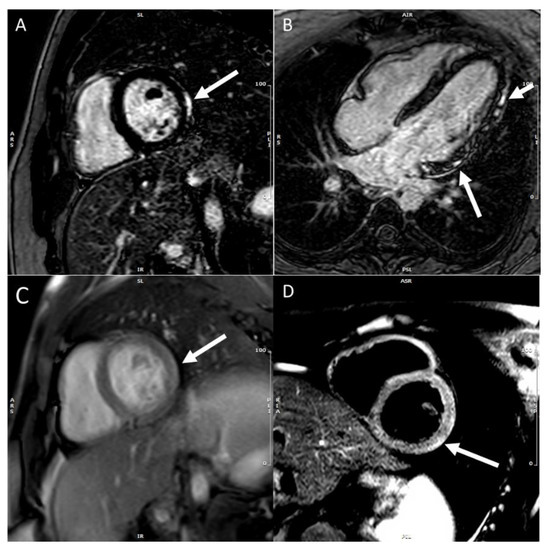

- Mahrholdt, H.; Wagner, A.; Deluigi, C.C.; Kispert, E.; Hager, S.; Meinhardt, G.; Vogelseberg, H.; Fritz, P.; Dippon, J.; C-Thomas, B.; et al. Presentation, patterns of myocardial damage, and clinical course of viral myocarditis. Circulation 2006, 114, 1581–1590. [Google Scholar] [CrossRef] [PubMed] [Green Version]